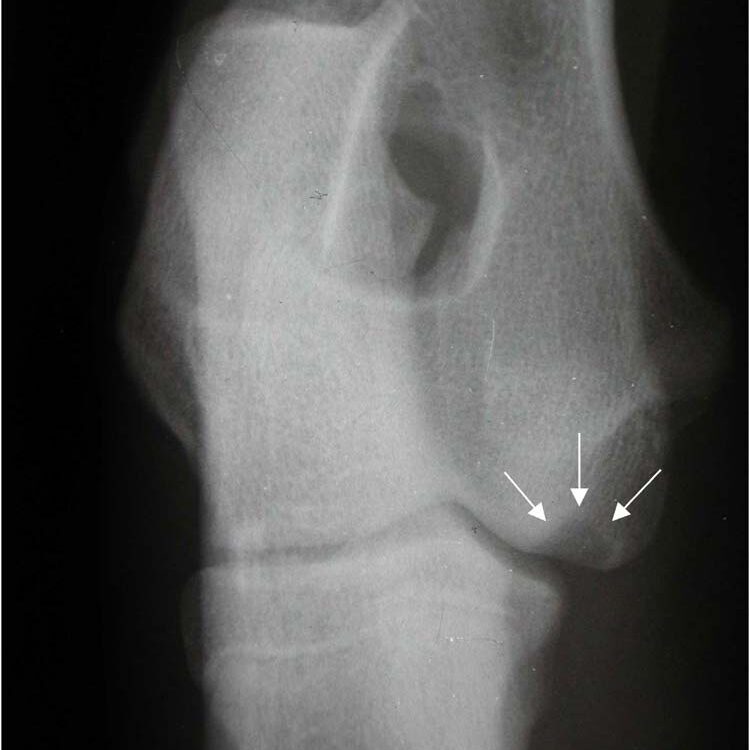

Humeral intracondylar fissure (HIF) (aka ‘incomplete ossification of the humeral condyle [IOHC])

Humeral intracondylar fissure is believed to be a stress fracture of the humeral condyle and is particularly prevalent in the English Springer Spaniel (ESS). Up to 14% of ESSs in UK have an abnormality within the humeral condyle which may indicate an increased risk for HIF or condylar fractures. HIF can cause chronic lameness and elbow pain and it can affect both elbows. Diagnosis is best made with CT scanning and, in most cases, surgical treatment is recommended.